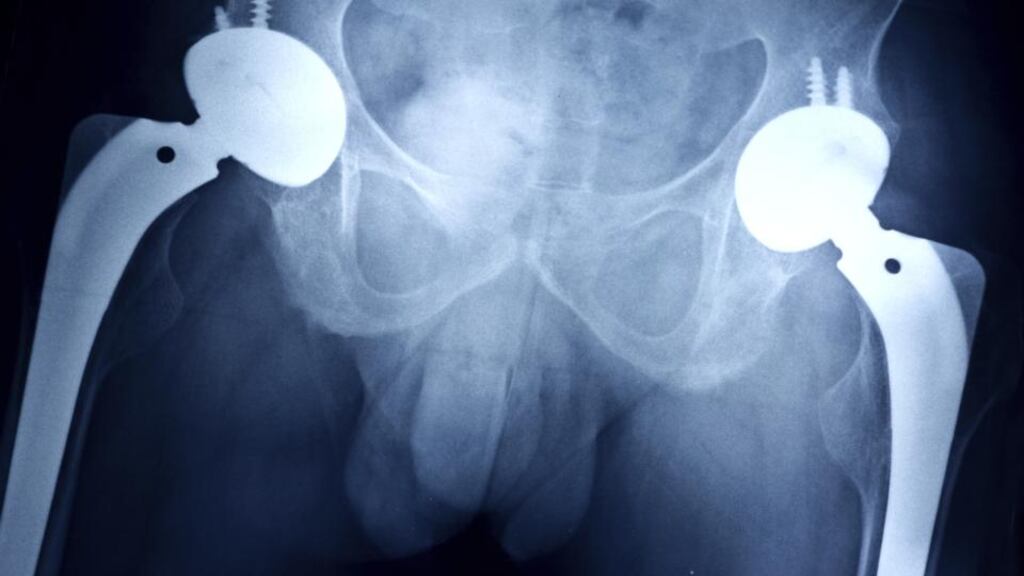

Orthopaedic implants and surgical equipment account for a large proportion of the vigilance reports received by the board, the 2012 annual report says. In particular, the ongoing problems associated with DePuy artificial hips and PIP breast implants have contributed to the rise in concerns reported to the IMB. The report says the consistent upward trend in the number of vigilance cases received is a result of greater clarity in reporting criteria, better communication between EU states and the IMB encouraging reporting on an ongoing basis.